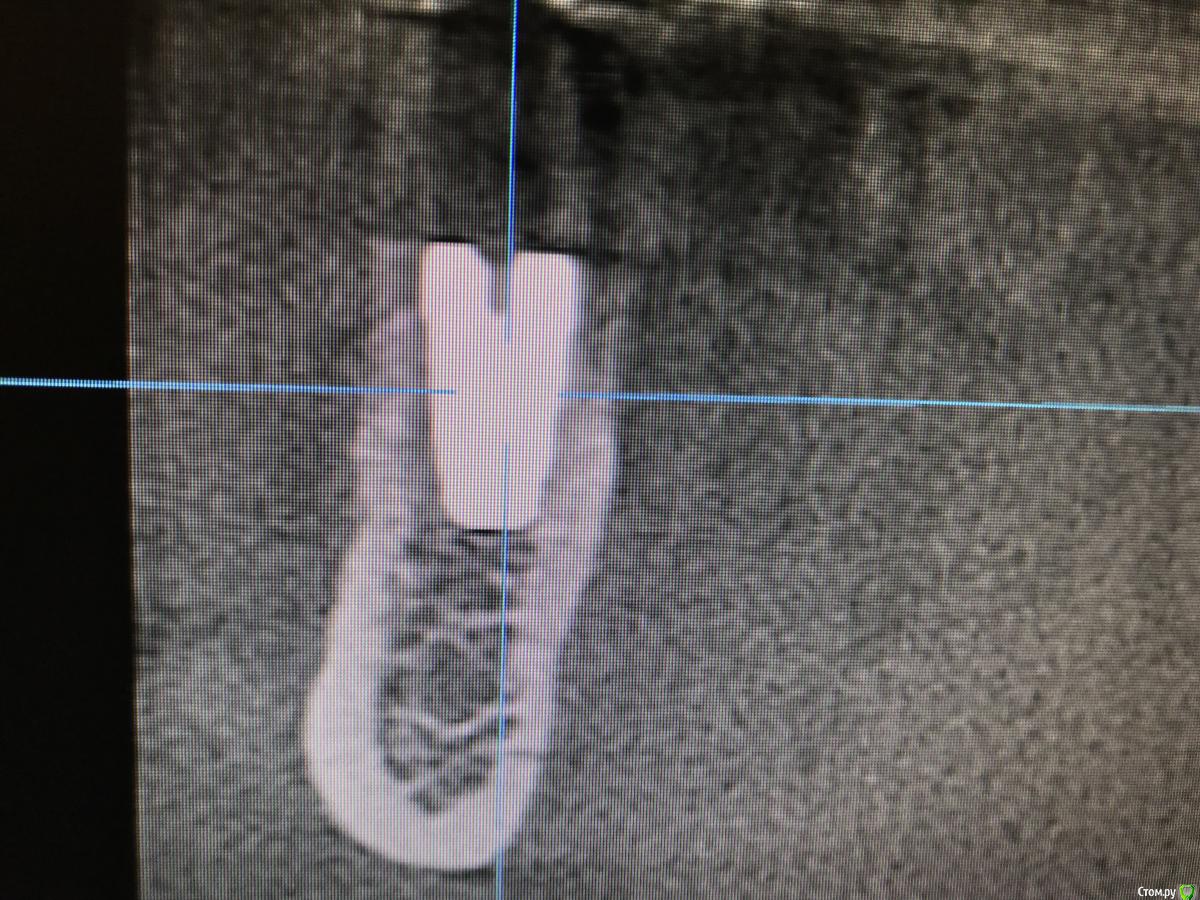

колесников Опубликовано 15 марта, 2019 Автор Поделиться Опубликовано 15 марта, 2019 Вот так выглядит интегрированый графт и соответственно не созревший. Время ожидания примерно равнозначное Ссылка на комментарий

колесников Опубликовано 16 марта, 2019 Автор Поделиться Опубликовано 16 марта, 2019 (изменено) Ну как бы тут все очевидно. Слева стала костью,справа нет. Но должен вам отметить,что даже в случае неудачи (как кажется)потери нет. Задача стояла не увеличить объём для имплантации или укрыть Имплант,а снять напряжение с вершины гребня и дать созреть десне. Имплант в нативной кости,он интегрирован,десна успела созреть за это время,возможно будет не так объёмно как хотелось бы,но у меня в запасе этап раскрытия ,фдм зарос ,есть с чем поработать. Все что не интегрировалось ,лизируется самостоятельно,выскребать ничего не нужно,ещё подождать. Изменено 16 марта, 2019 пользователем колесников Ссылка на комментарий